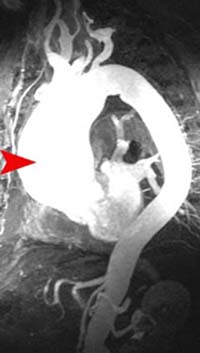

Shown above are an axial image (left) and a maximum intensity projection (MIP) MRA (right) from a patient with an ascending aortic dissection, which would be classified as Stanford Type A. An intimal flap can clearly be seen in the axial image. However, the MIP image shows only the resulting aneurysmal dilation and not the intimal flap, which is a limitation of the technique.